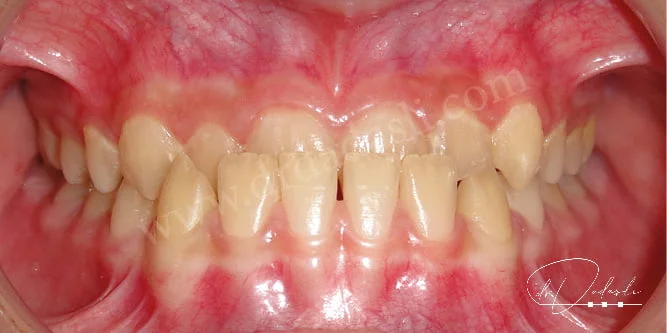

- Ters kapanış (Şekil 2 ve Şekil 3) – bu durumda alt ön dişler üst ön dişlerin gerisinde bulunmaları gerekirken önünde konumlanmıştır. Bu durumun ortodonti bilimindeki ismi Sınıf III maloklüzyondur.